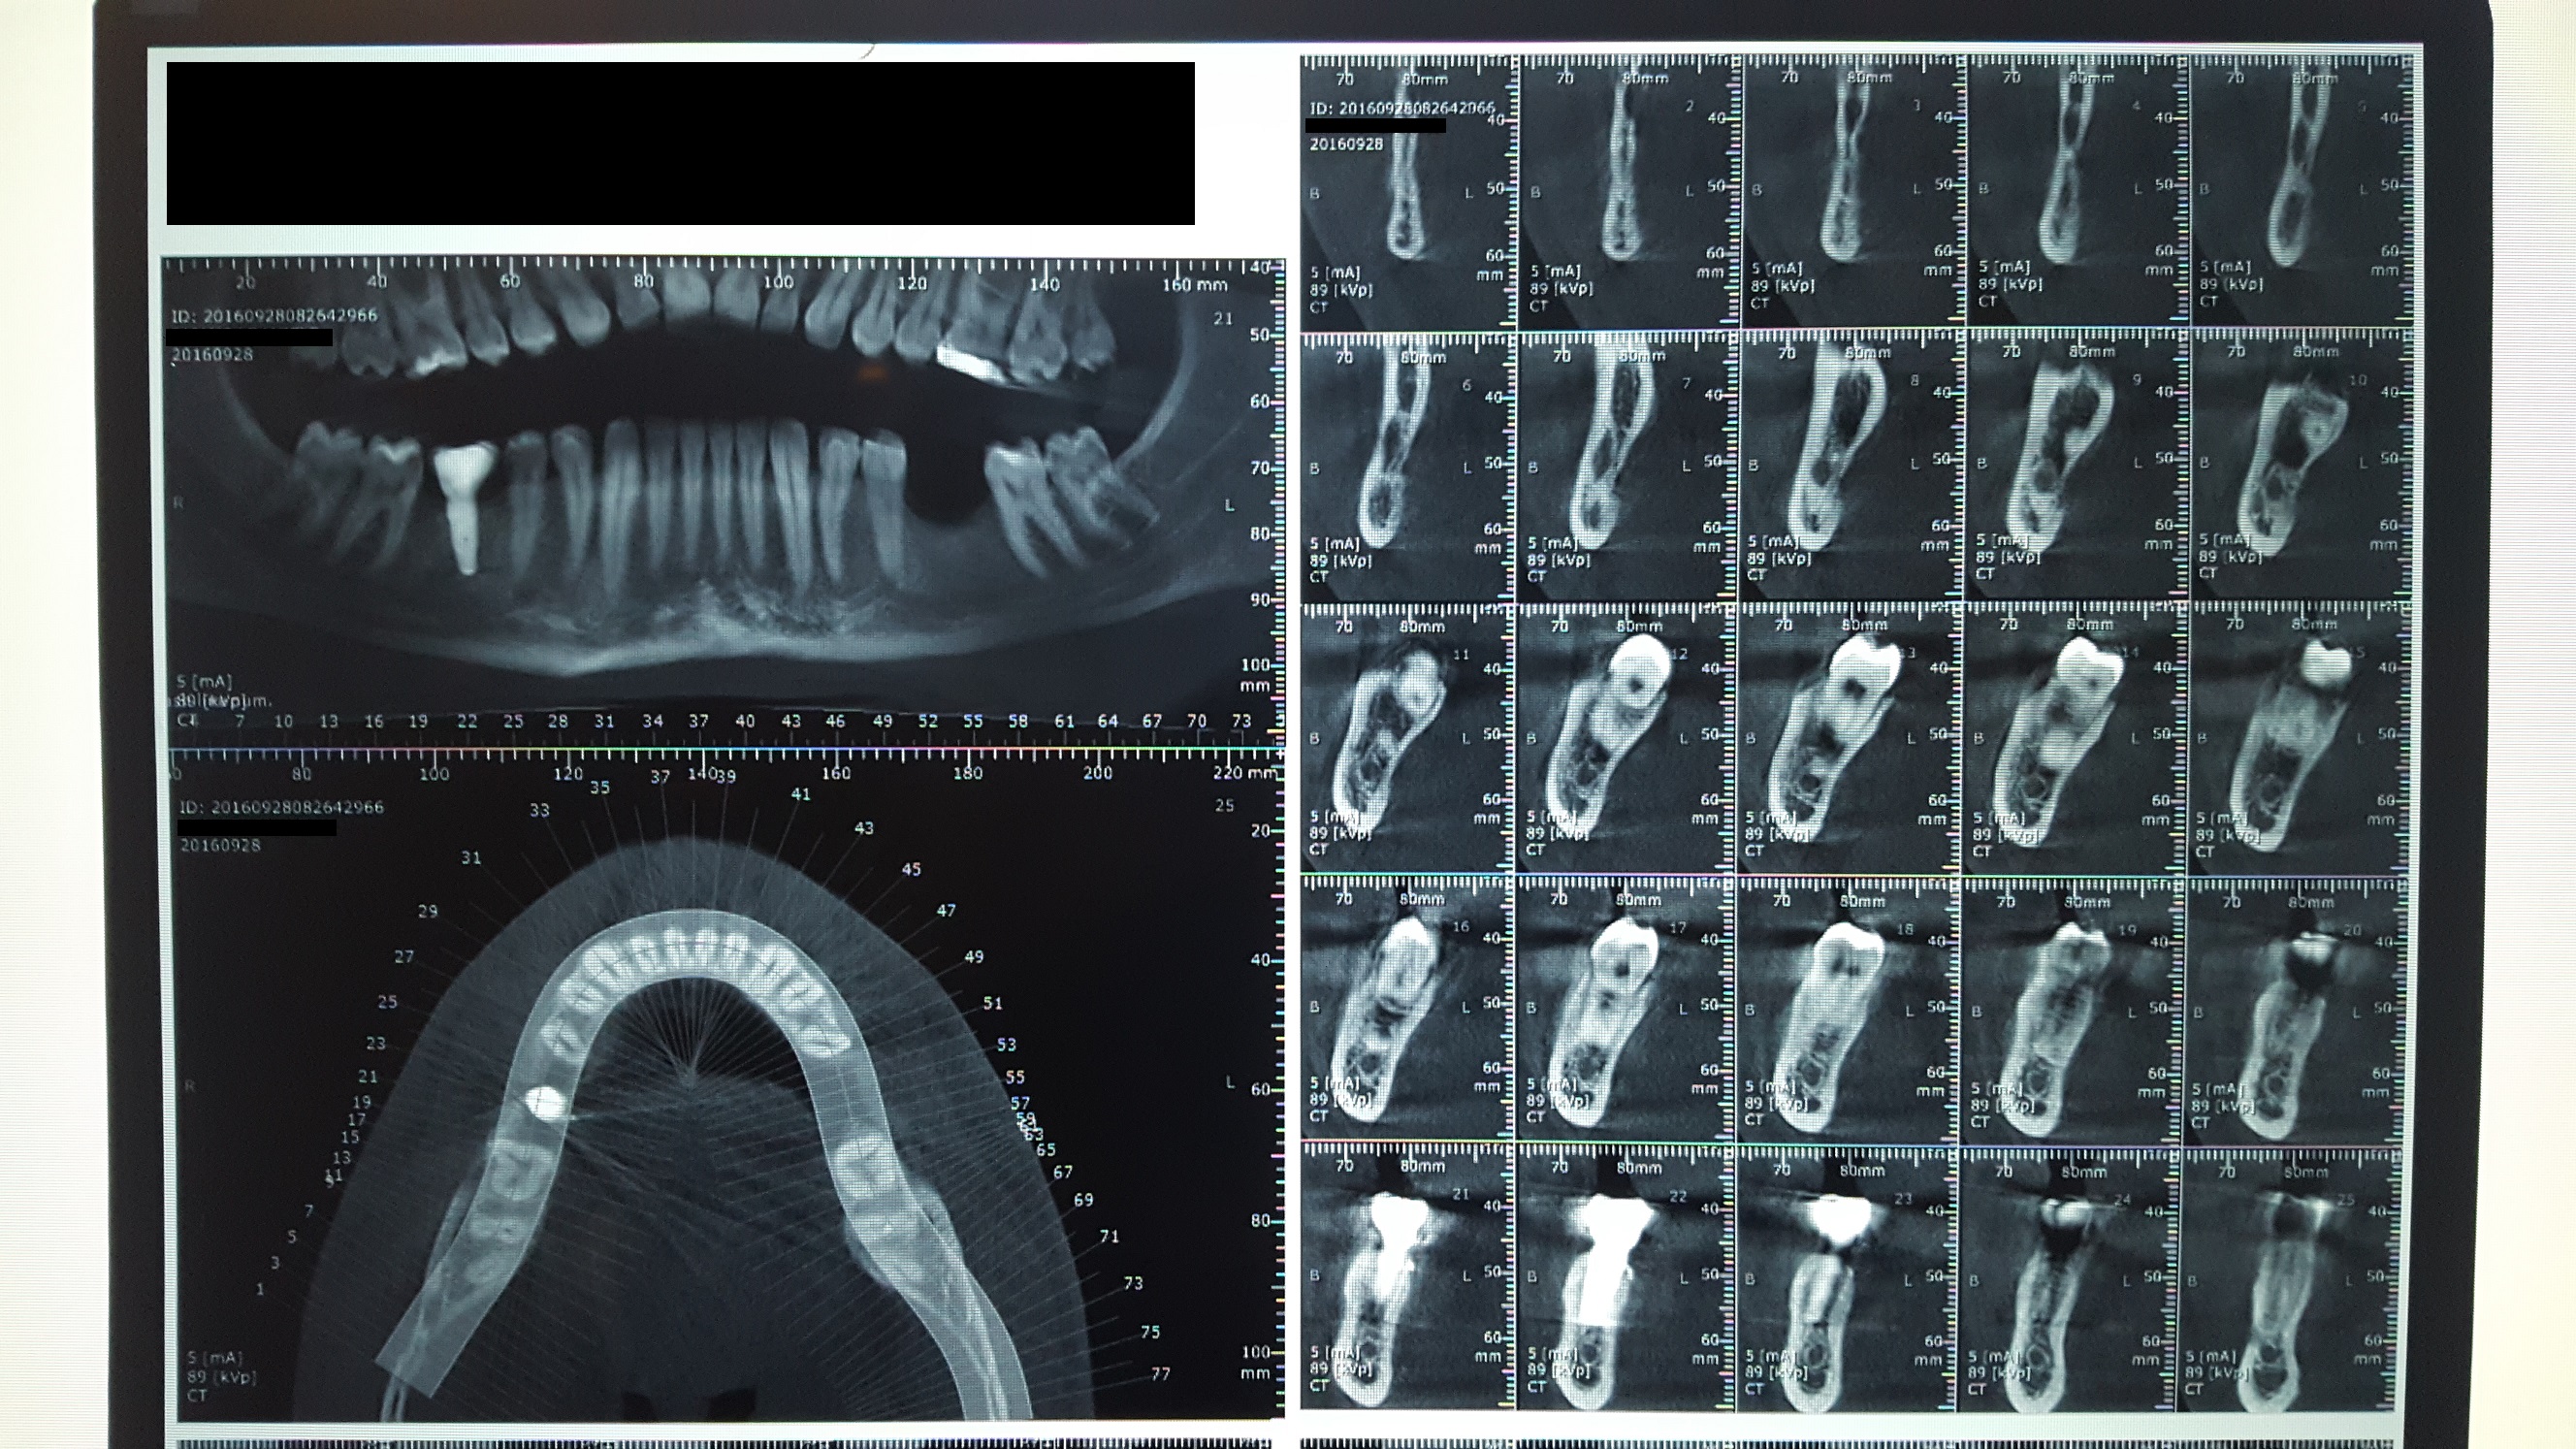

Ho eseguito parecchie panoramiche e due "tac cone beam" (una prima dell'intervento osseo usata "solo" per capire come inserire l'impianto) per scoprire la causa di questo bizzarro problema.

Ha fatto controllare che il dente numero 47 risponda correttamente a tutti i test di vitalità? Sondaggio? Intendo in tutti i modi possibili, compreso il test utile per rilevare eventuali infrazioni coronali - radicolari (sindrome del dente fratturato). A livello radiografico non sembrano esserci problemi (faccio riferimento alla radiografia in cui i punti di contatto della corona sono corretti) per l'impianto (osteointegrazione nella norma) e per la corona protesica stessa, quindi, con il beneficio del dubbio e non potendola visitare, da quel punto di vista sembrerebbe tutto ok.

Buongiorno Daniele, la sua vicenda é piuttosto singolare ed a distanza sembra impossibile far diagnosi, visto che altri specialisti non hanno trovato una soluzione pur avendo avuto il caso sotto mano. Lei riferisce sintomi al 47 ma l'impianto è in posizione 46 e dalle radiografie inviate sembra abbastanza distante da non interferire direttamente così come sembra normale la architettura dell'osso alveolare. Ci dice inoltre che i sintomi persistono anche dopo la rimozione della corona protesica. Non ci dice però se il 47 è positivo ai test di vitalità o alla percussione, se fa male alla masticazione, se è presente o meno un sondaggio patologico, un sanguinamento o un vacillamento o altri segni di compromissione . In assenza di altri segni o sintomi potrebbe rivelarsi necessario un intervento esplorativo per verificare in vivo la vitalità dell' osso alveolare della zona dei molari in oggetto. Non si perda d'animo e prosegua le indagini. Poi ci faccia sapere. Cordiali saluti.